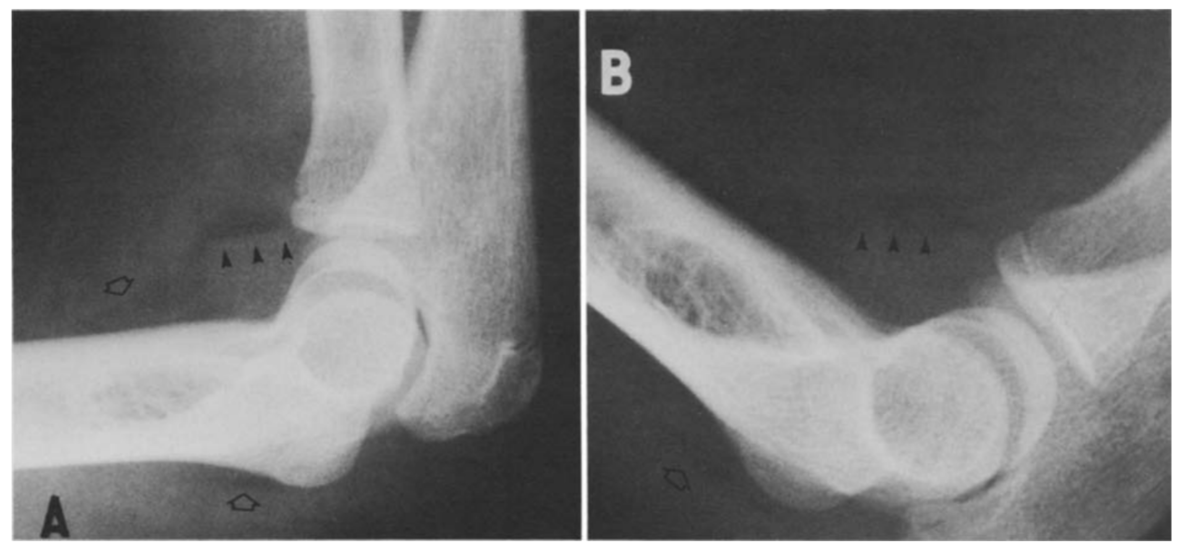

③ 肘关节

肘关节积脂血症与肘关节脂肪垫征原理类似,在肘关节骨折后关节腔内积血将肘关节脂肪垫抬高,高度提示桡骨小头骨折。

病例7 一例10岁患者肘关节外伤,侧位可见明显关节积脂血症。